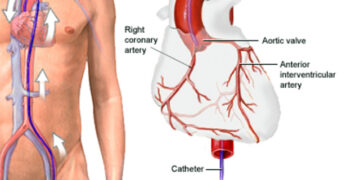

সুমাইয়া কাফী করোনারি এনজিওগ্রাম কোনো চিকিৎসাপদ্ধতি নয়। এটি এক্স–রে ইমেজিং পদ্ধতি ব্যবহার করে হৃদ্যন্ত্রের রক্তপ্রবাহ কোথাও বাধাগ্রস্ত হচ্ছে কি না,...

Read moreডা. আসিফ মনোয়ার, সহযোগী পরামর্শক, হৃদ্রোগ বিভাগ, স্কয়ার হাসপাতাল লিমিটেড দেশে হৃদ্রোগীর সংখ্যা অনেক। নানা ধরনের হৃদ্রোগের জন্য রয়েছে বিভিন্ন...